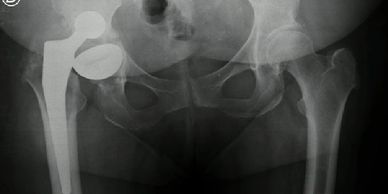

Mirá cómo recuperamos la movilidad en un caso de artrosis severa y deformidad acetabular mediante tecnología 3D de alta precisión. Planificación preoperatoria en 3D para cirugía de cadera con artrosis severa e importante deformidad acetabular. Se imprimieron biomodelos en 3D y guías para la correcta colocación de los componentes protésicos. De esta manera, se logró restaurar la longitud de las piernas y se eliminó el dolor invalidante que presentaba el paciente.

Paciente con artrosis severa y deformidad ósea que dificultaba la colocación acetabular. Con tomografía realizamos planificación 3D y diseñamos una guía quirúrgica personalizada impresa en 3D. En quirófano replicamos el plan: posicionamiento preciso del componente y restauración del centro de rotación. La tecnología 3D aporta más precisión, seguridad y predictibilidad en casos complejos.